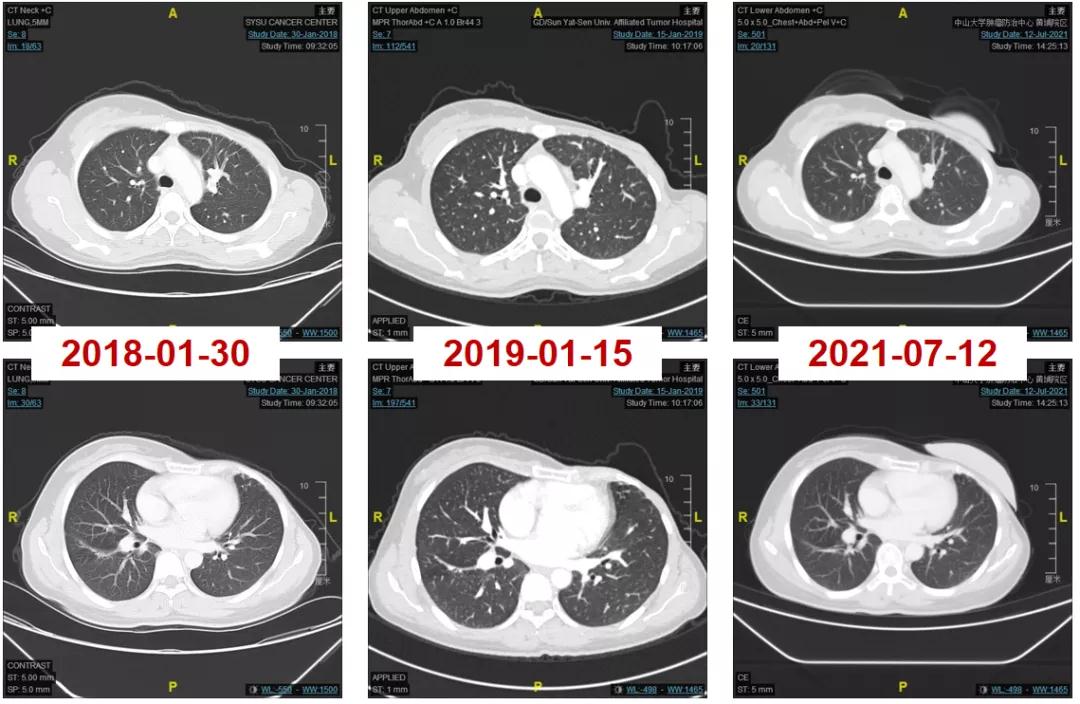

2016-06-01复查CT:右肺下叶上段团块状肿物(图1),考虑转移。

图1

2016-12-06开始使用T-DM1(恩美曲妥珠单抗)方案治疗,首次疗效评估PR,后续最佳疗效CR(图2-3)。

图2

图3